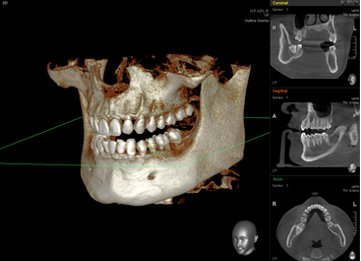

교정치료는 눈으로만 확인하고 정밀한 치료계획을 세울 수 없습니다.

구강 전반 및 얼굴뼈 부위까지 광범위한 진단을 통해 육안으로는 파악하기 어려운 부분까지 살펴볼 수 있습니다.

약2년간 이어지는 치료과정동안 의료진의 판단에 도움을 주어 올바른 치료가 될 수 있도록 도와주는 장비입니다.